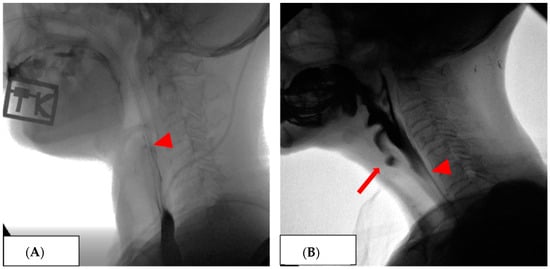

Figure 1 shows the findings of the VFSS with an NGT inserted. Patients assigned to Group 2 had no aspiration when oral swallowing was attempted with an NGT inserted during the VFSS (Figure 1A). These patients were allowed an oral feeding trial with an NGT inserted. However, the patients assigned to Group 3 showed aspiration when they tried to swallow orally with an NGT inserted (Figure 1B). These patients were not allowed to undergo an oral feeding trial with an NGT inserted.

Figure 1. The findings of the VFSS with an NGT inserted. (A): Patients assigned to Group 2 had no aspiration when oral swallowing was attempted with an NGT inserted (arrowhead) during the VFSS (Video S1). (B): Patients assigned to Group 3 showed aspiration (arrow) when they tried to swallow orally with an NGT inserted (arrowhead) (Video S2).